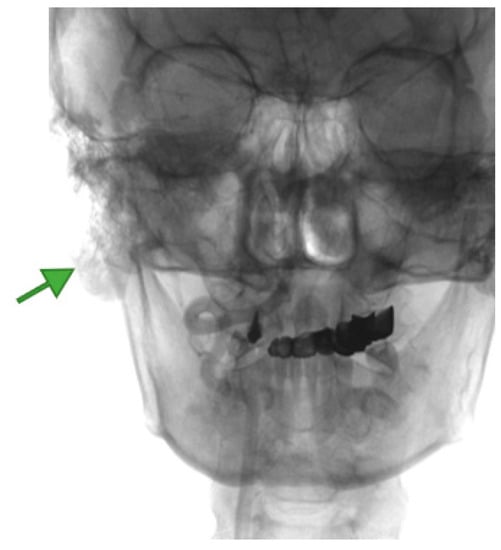

4. Imagery in Extracranial FNSs